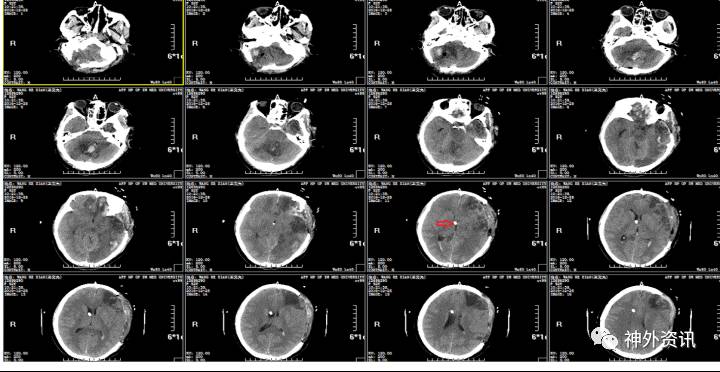

2016.12.20:术后第1天,患者意识仍昏迷,自主呼吸尚可,出现双瞳不等大,左瞳3.0mm,右瞳2.0mm,光反射消失,复查头颅CT发现,原小脑挫裂伤灶出血明显增加,周围水肿明显,环池仍不清。

小脑血肿增加:约4.6cm*5.1cm*2cm

空心箭头:血浆引流管;实心箭头:脑室积血。

2016.12.21:患者生命体征平稳,自主呼吸,意识呈浅昏迷,双瞳不等大,左瞳直径3.0mm,右瞳2.5mm,光反射均迟钝,复查头颅CT示:环池欠清,脑室积血,脑组织稍肿胀,未见明显脑积水,暂不考虑手术,予以止血、脱水、促性、预防感染及癫痫处理,动态头颅CT密切监测患者病情变化。